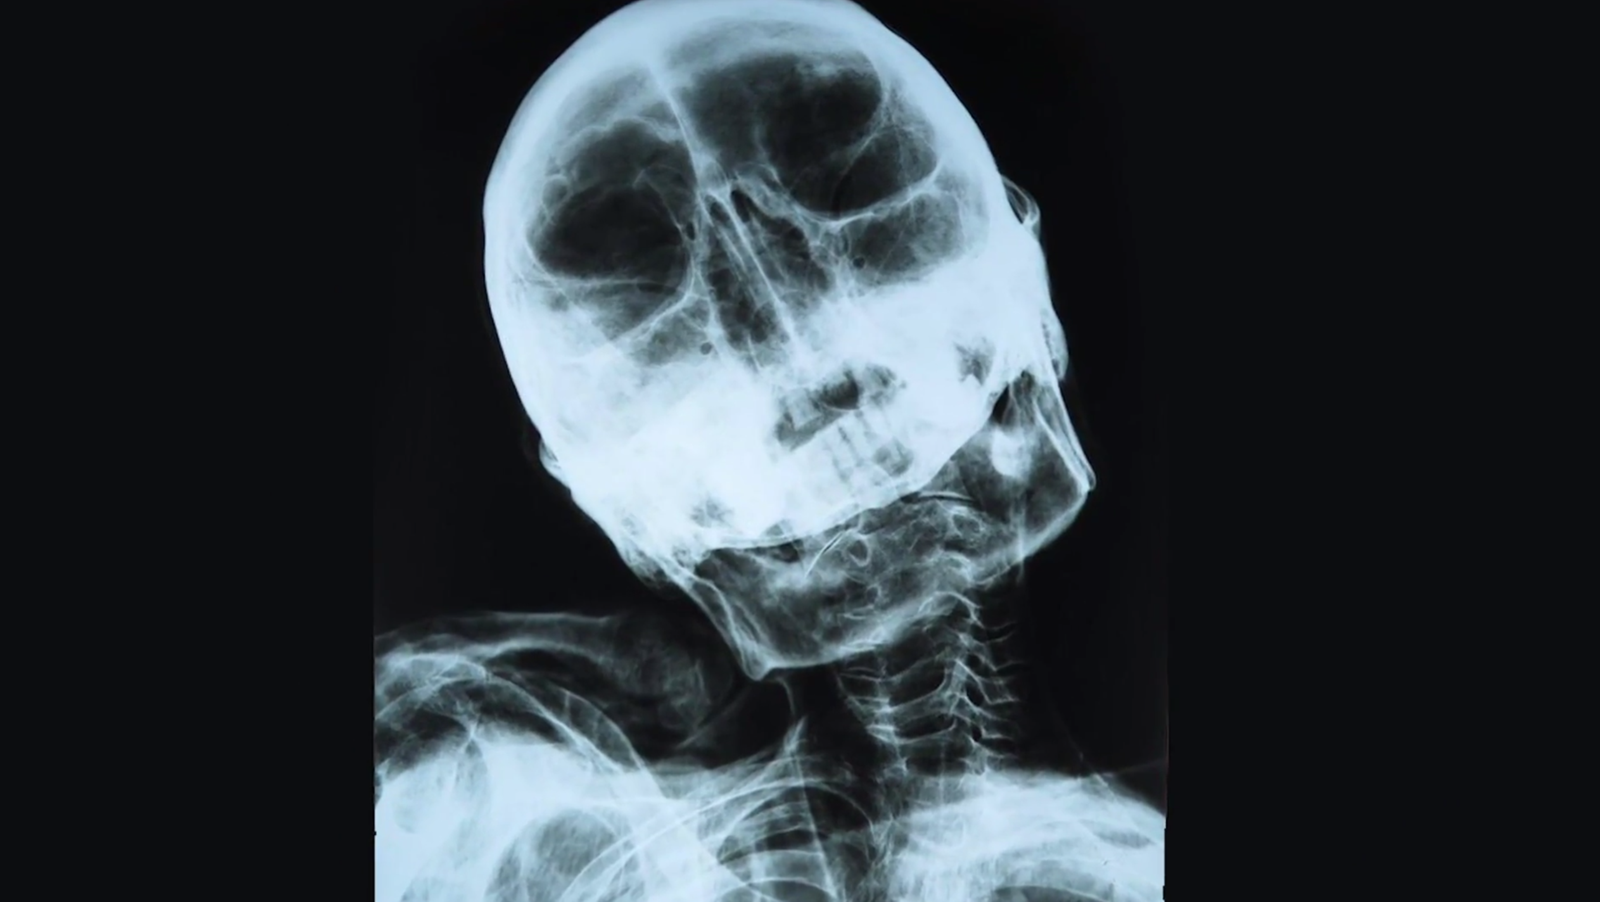

Pero cuando se mira a los rayos X, se puede ver que esa es la anatomía.

Esos huesos crecieron juntos.